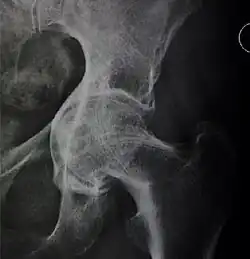

Crowe classification

In 1979 Dr. John F. Crowe et al. proposed a classification to define the degree of malformation and dislocation. Grouped from least severe Crowe I dysplasia to most severe Crowe IV.[13] This classification is very useful for studying treatment results.

Rather than using the Wiberg angle because it makes it difficult to quantify the degree of dislocation they used 3 key elements to determine the degree of subluxation: A reference line at the lower rim of the "teardrop", junction between the femoral head and neck of the respective joint and the height of the pelvis (vertical measurement). They studied anteroposterior pelvic x-rays and drew horizontal lines through the lower rim of a feature called "teardrop". The distance between this line and the middle lines of the junction between femur head and neck gave them a measure of the degree of femur head subluxation. They further established that a "normal" diameter of the femur head measures 20% of the height of the pelvis. If the middle line of the neck-head junction was more than 10% of the pelvis height above the reference line they considered the joint to be more than 50% dislocated.[13]

The following types resulted:[13]

Class Description Dislocation

Crowe I Femur and acetabulum show minimal abnormal development. Less than 50% dislocation

Crowe II The acetabulum shows abnormal development. 50% to 75% dislocation

Crowe III The acetabula is developed without a roof. A false acetabulum develops opposite the dislocated femur head position. The joint is fully dislocated. 75% to 100% dislocation

Crowe IV The acetabulum is insufficiently developed. Since the femur is positioned high up on the pelvis this class is also known as "high hip dislocation". 100% dislocation